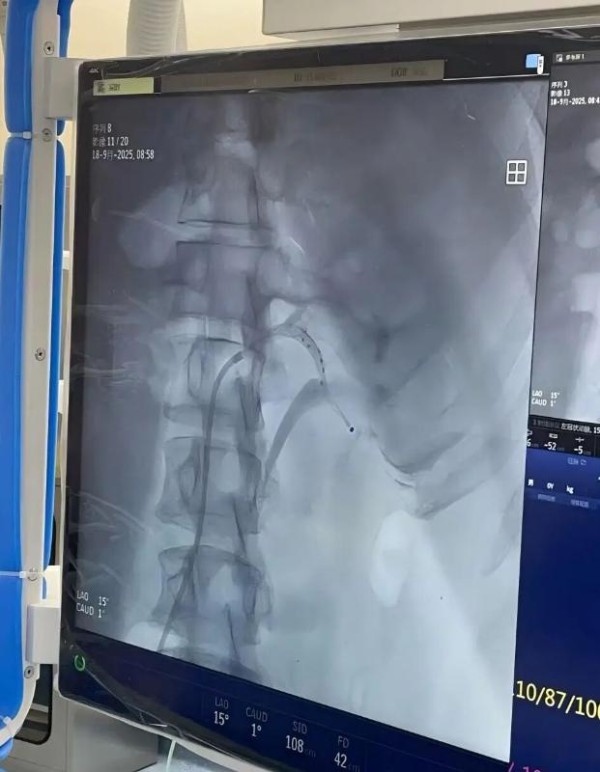

就在去年,高血压治疗的新技术-肾动脉交感神经射频消融术(RDN)相关设备通过我国药品监督管理局审批上市,成为难治性高血压或依从性差的高血压患者的治疗新希望。9月18日,上海交通大学医学院附属瑞金医院嘉定院区成功为一位高血压患者实施了RDN手术,患者血压得到明显改善。

瑞金医院嘉定院区刘常远主治医师接诊后将其收入病房,在陈歆主任指导下对张先生进行了全面细致的评估,重点在于筛查继发性高血压及评估靶器官损害情况,最终诊断原发性高血压,结合患者肾动脉情况明确其符合RDN手术指征,完善术前检查后为其制定了周密的手术方案。手术当天,由许建忠主任作为主刀医师,刘常远主治医师、李明春主治医师作为助手,凭借娴熟的介入技术,将肾动脉消融导管精准送达双侧肾动脉及副肾动脉,通过射频能量对双侧肾动脉交感神经进行消融。整个手术历时约1.5个小时,共消融56个点位,全程患者无明显不适,术后在护理团队的精心照护下,患者生命体征平稳,感觉良好。

RDN全称肾动脉交感神经射频消融术,是近年来治疗难治性高血压的一项创新微创介入技术,通过减少肾脏交感神经兴奋,抑制肾素-血管紧张素-醛固酮系统(RAAS)的激活,降低肾血管阻力和水钠潴留,从而实现长期血压控制,为药物治疗血压控制不佳及药物不耐受等患者提供了新的治疗选择。